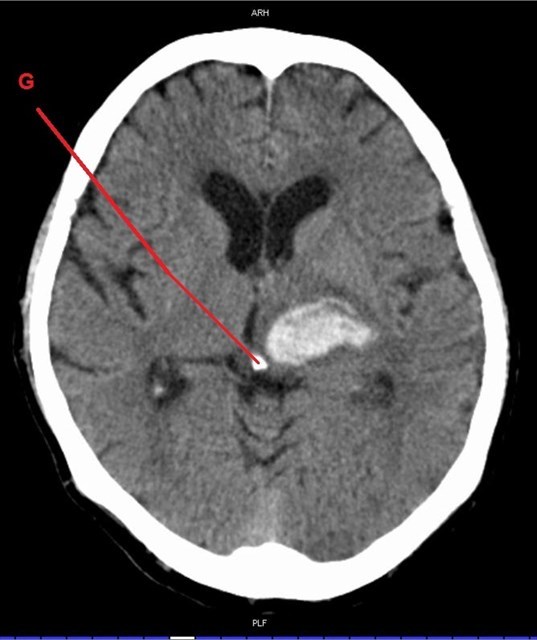

A dál co potřebujete k získání finálních souřadnic? Trocha z té zdravotnické praxe. Správný geokačer má silně vyvinutý smysl pro všímání si detailů, skrytých souvislostí a tak podobně. Princip je jednoduchý. Nepůjde o žádnou kdoví jak složitou matematickou šifru s IT podtextem. V budoucích několika minutách, hodinách či dnech se z Vás stanou radiologové (lékaři zabývající se zobrazovacími technikami) a anatomové. Tak Vás jistě nepřekvapí několik obrázků, na kterých bude vyznačen útvar, který musíte poznat a latinsky (pokud jiným jazykem, tak Vás na to upozorním) pojmenovat. Myslím, že vše bude jasné. Tak jdeme na to…

G - počet písmen v názvu útvaru/kalcifikovaného u (téměř?) všech dospělých (řecky, 2 slova)